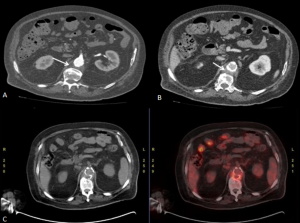

MAGNETIC RESONANCE IMAGING (MRI)

MRI offers superior soft-tissue contrast and enables non-contrast visualisation of the renal collecting system, making it particularly valuable in patients with renal impairment.

RPF is typically hypointense on T1-weighted images with variable intensity on T2-weighted images as well as in apparent diffusion coefficient values depending on the degree of active inflammation [2,3].

NUCLEAR IMAGING

FDG-PET/CT enables reliable assessment of metabolic activity in idiopathic retroperitoneal fibrosis, supporting diagnosis, treatment monitoring and prognostic stratification. Increased FDG avidity is associated with active disease and may predict response to immunosuppressive therapy, while metabolically inactive tissue can guide ureteric stent removal. Although CT and MRI remain the preferred modalities for routine follow-up, FDG-PET/CT is valuable when residual disease activity is uncertain. Higher SUVmax and contrast-enhancement scores correlate with inflammatory markers, with SUVmax > 2.76 accurately identifying active disease.